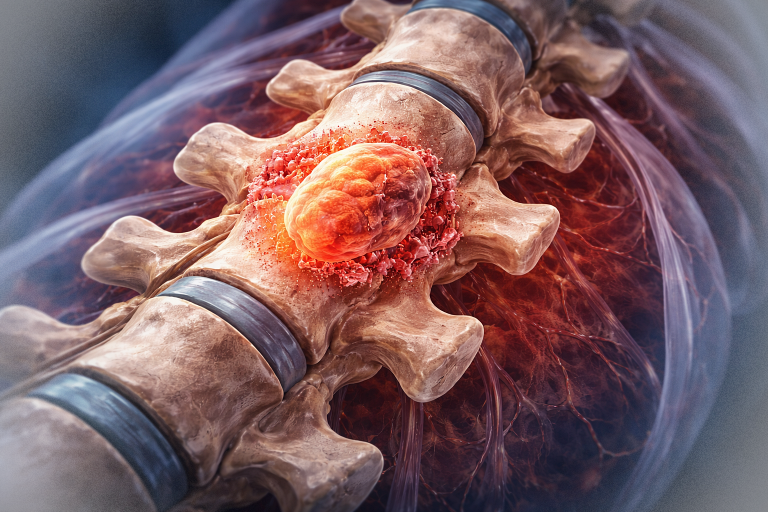

Din punct de vedere histopatologic, craniofaringioamele derivă din resturi epiteliale embrionare ale pungii Rathke, o structură embrionară implicată în dezvoltarea hipofizei anterioare. Tumorile sunt împărțite în două subtipuri principale:

- Adamantinomatose: cele mai frecvente, întâlnite predominant la copii. Prezintă chisturi mari, calcificări extinse și un epiteliu scuamos, cu arii keratinoase (keratină lamelară) și colesterol în interiorul chisturilor.

- Papilare: apar predominant la adulți, au calcificări rare și sunt constituite din structuri epiteliale papilare fără keratină.

În practica clinică, distincția între cele două subtipuri este importantă, deoarece acestea prezintă particularități ale comportamentului biologic și evoluției clinice.